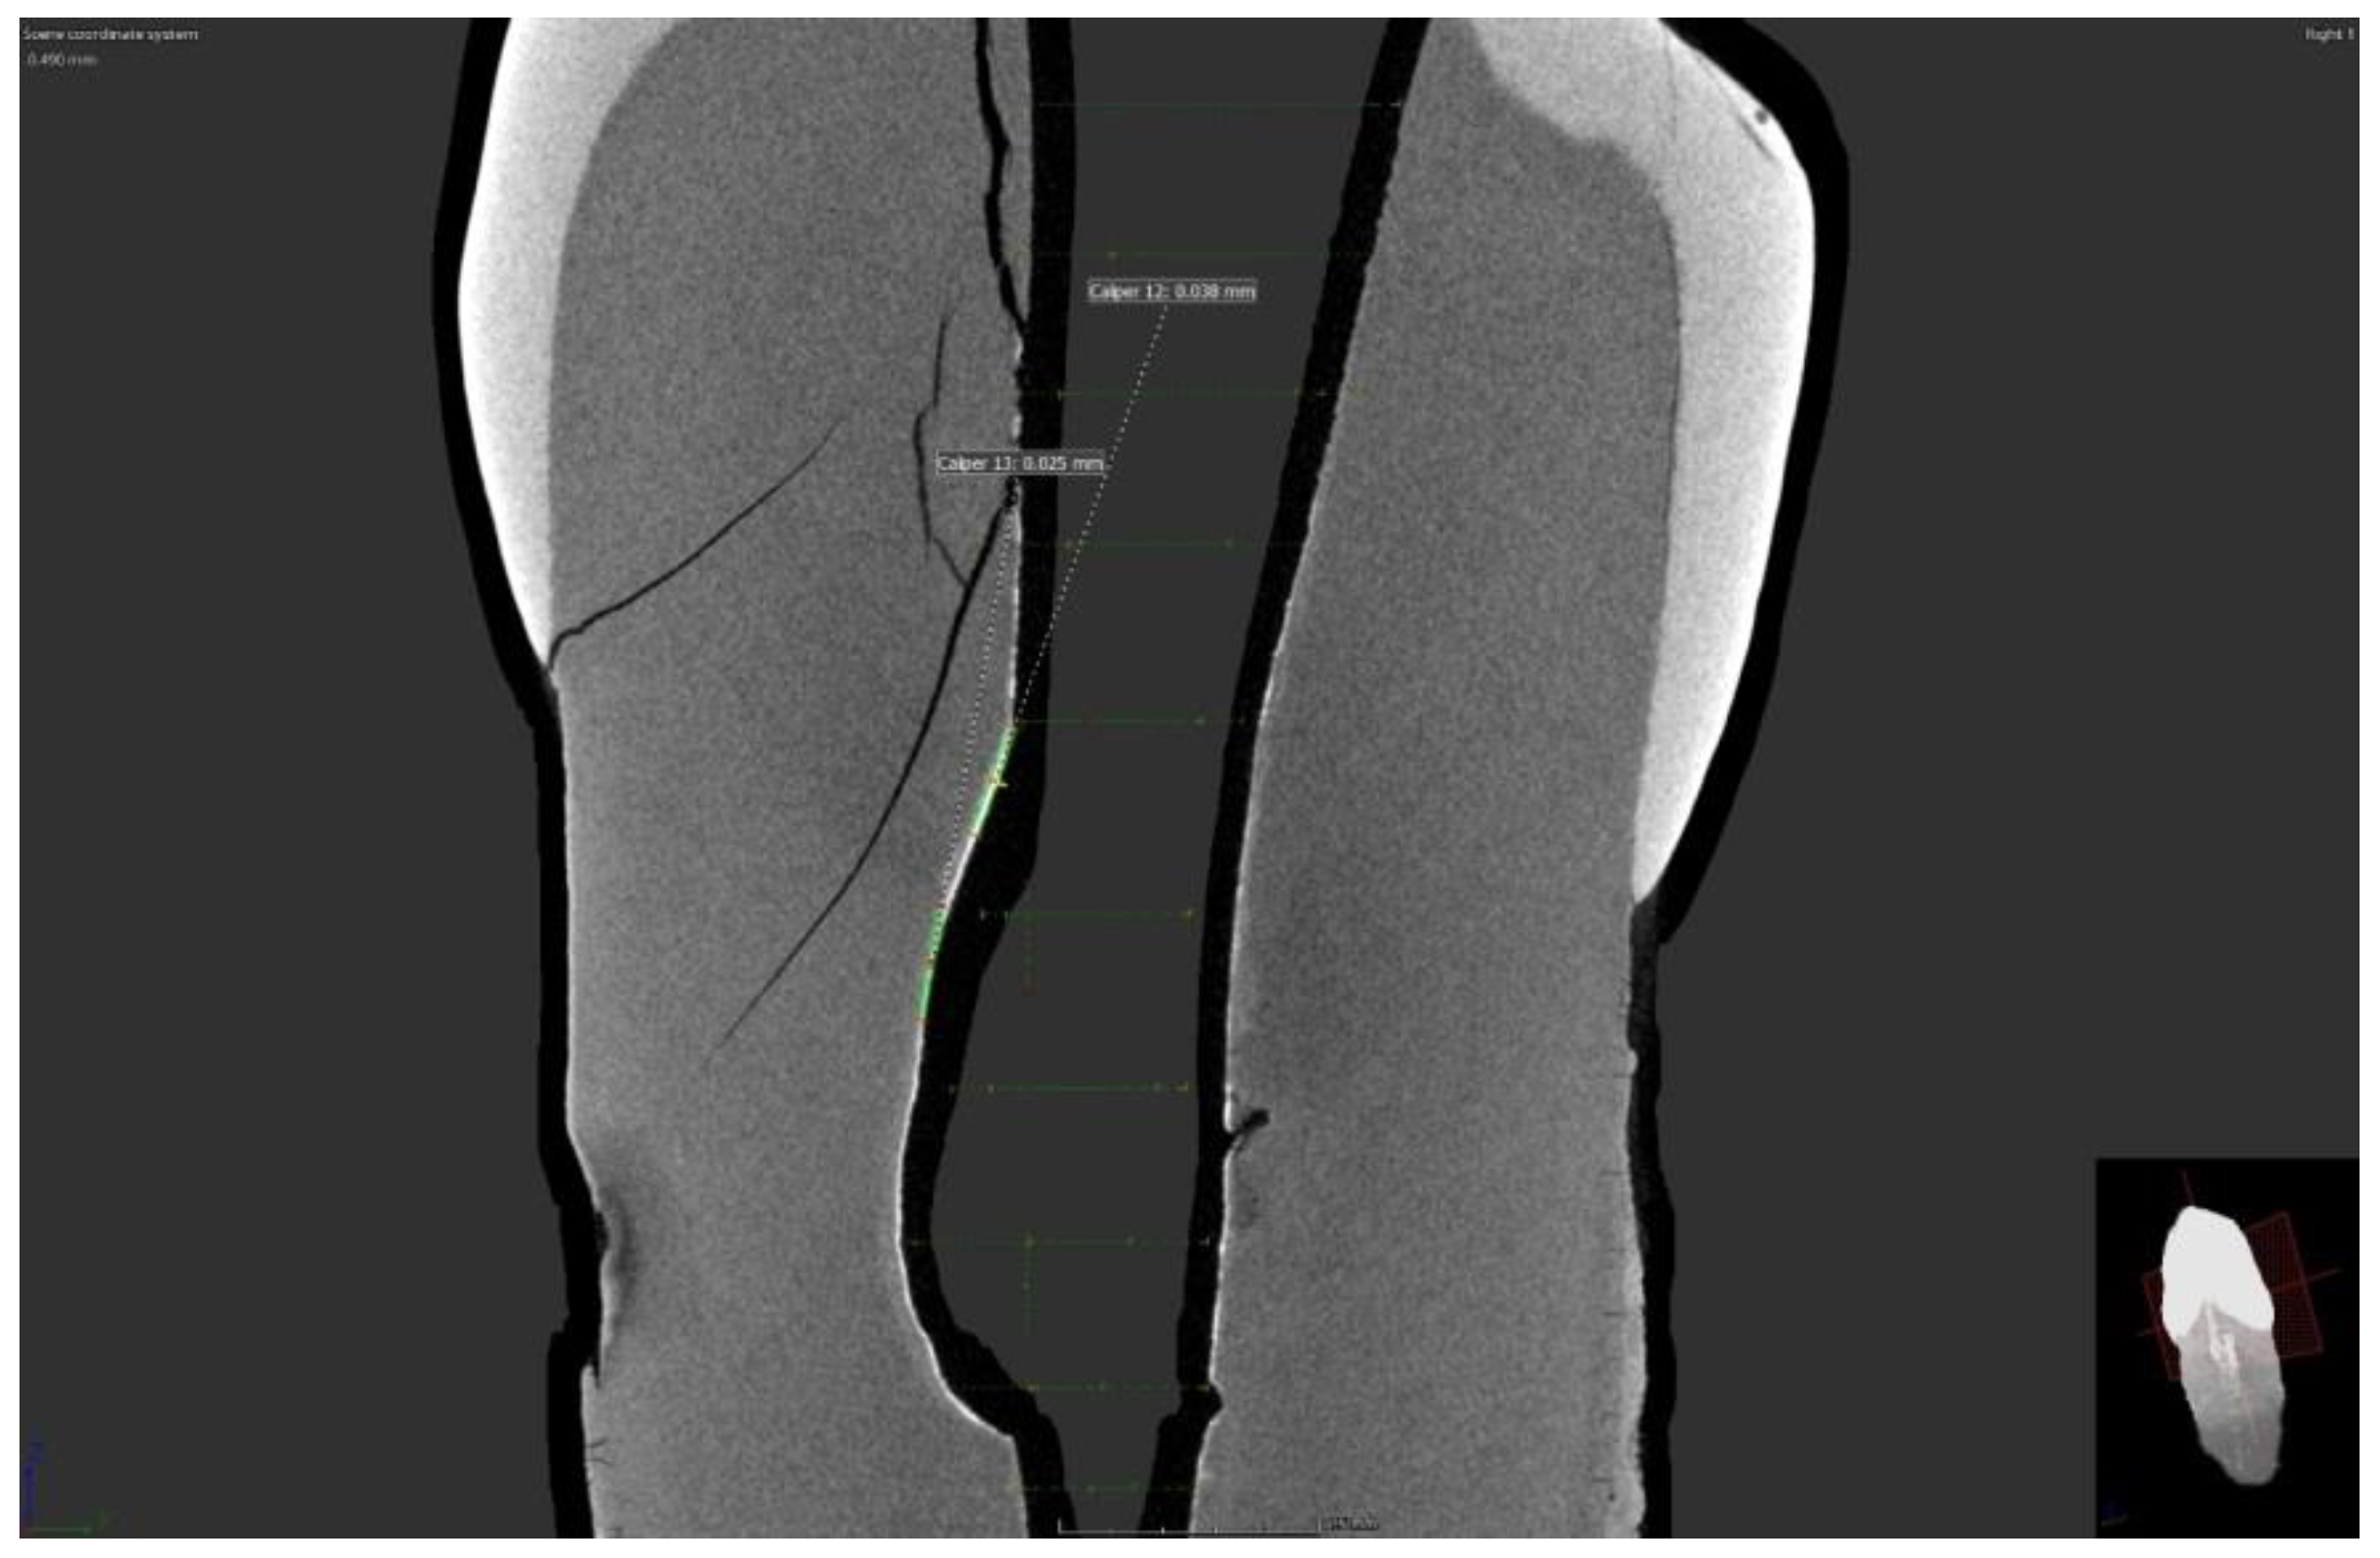

Micro-CT scans showed the presence of a silver film on all samples of both groups with removed and preserved smear layers. However, imaging of these films shows an uneven distribution of silver film over the dentinal surface (Figure 1 and Figure 2).

A series of horizontal vertical images showed the uneven distribution of the silver film over the inner surface of the root canal, but in some scans, it was even possible to measure the penetration depth or the thickness of the silver film. In samples with a removed smear layer, the penetration depth ranged from 0.023 to 0.028 nm. Moreover, in the group with preserved smear layer, the thickness of the silver film ranged from 0.023 to 0.066 nm in different scans.

Figure 1. Micro CT scan of sample with removed smear layer.